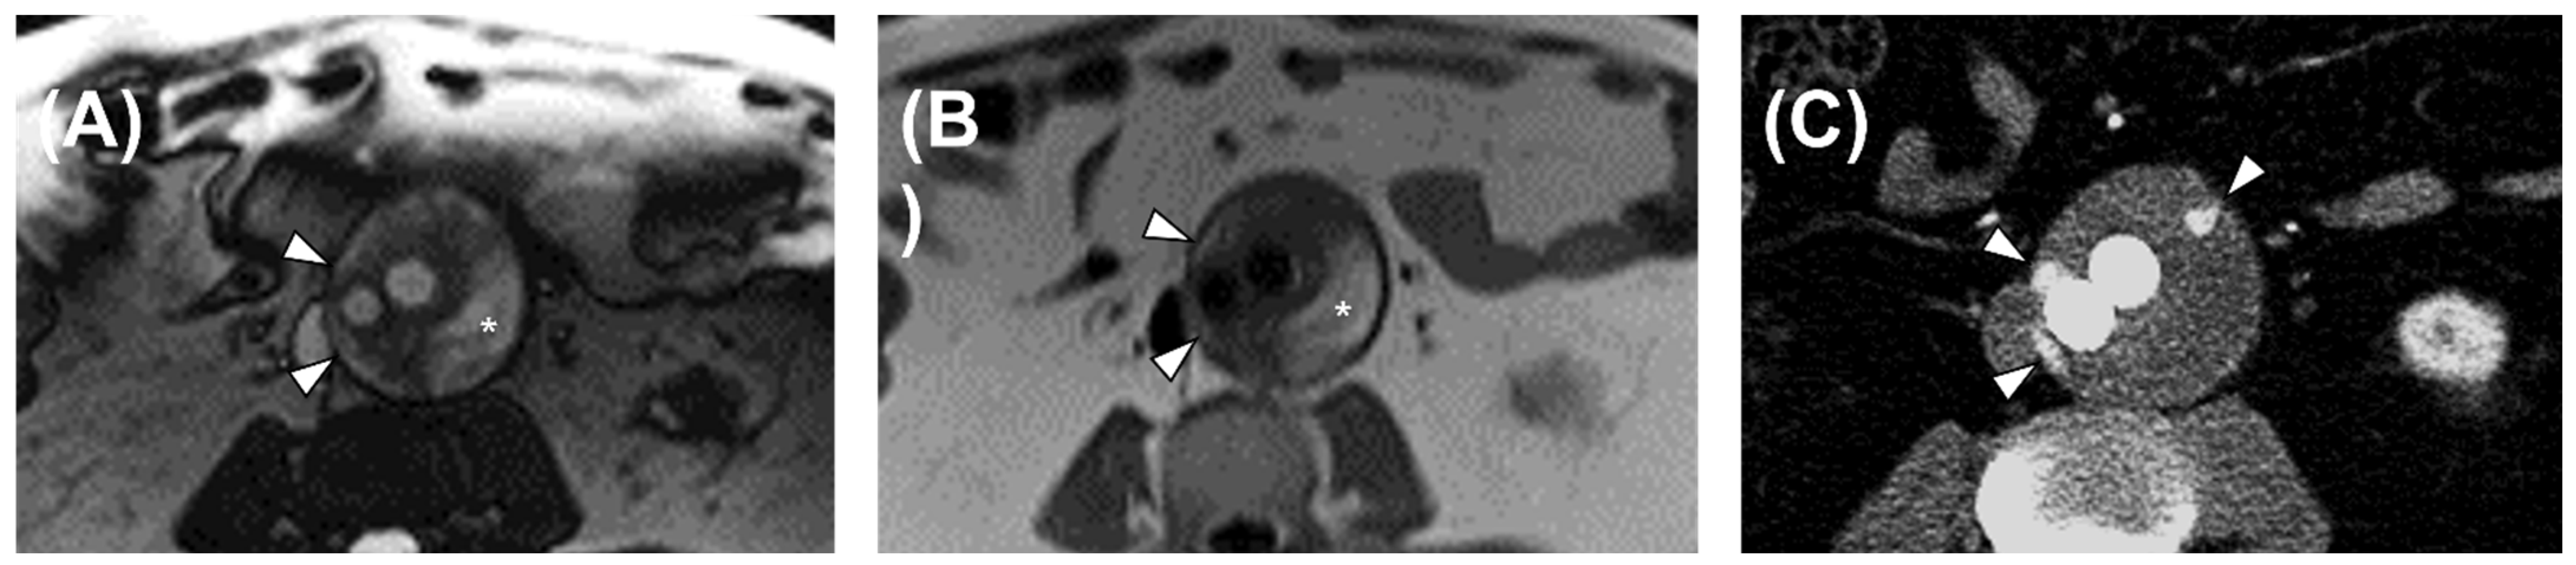

3.3. Flow MRI Diagnostic Performance

4. Discussion